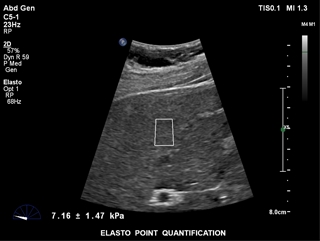

ElastPQ is an easy-to-use method of obtaining tissue stiffness values of the liver on a predefined ROI. Using real-time imaging as a guide, the ROI is placed over the area of interest and tissue stiffness data such as AVG, MEAN, and IQR are obtained and displayed in seconds. Multiple samples can be recorded and liver tissue report generated from the results.